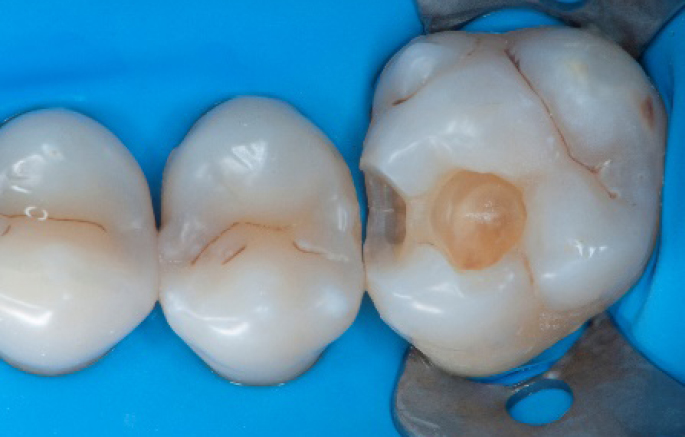

Step 8:

Transformation of class II into class I, restoring the interproximal wall with Spectra ST4 composite in shade A2.

Step 9:

Transformation of a big class I into a small class I, using SDR® flow+ material in one increment up to 4 mm.